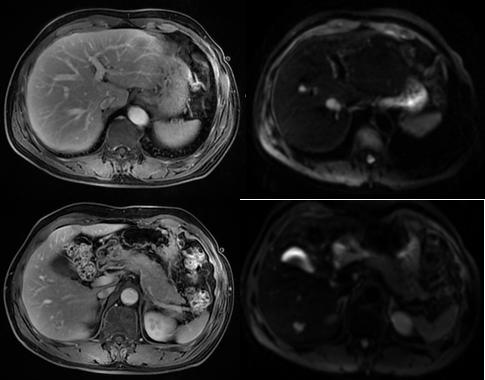

MR随访示病灶保持基本稳定(2020.2)

MR示肝脏转移较前有所增大(2020.11)

MR示经过放疗病灶基本消失(2021.)